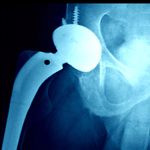

Hip replacement is a wonderful operation which gives a patient painfree movement and a new lease on life. Technology and advances in human hip replacement have now allowed this operation to be performed in animals as this happy tiger can attest. Read more If you want to read more about hip replacement click here